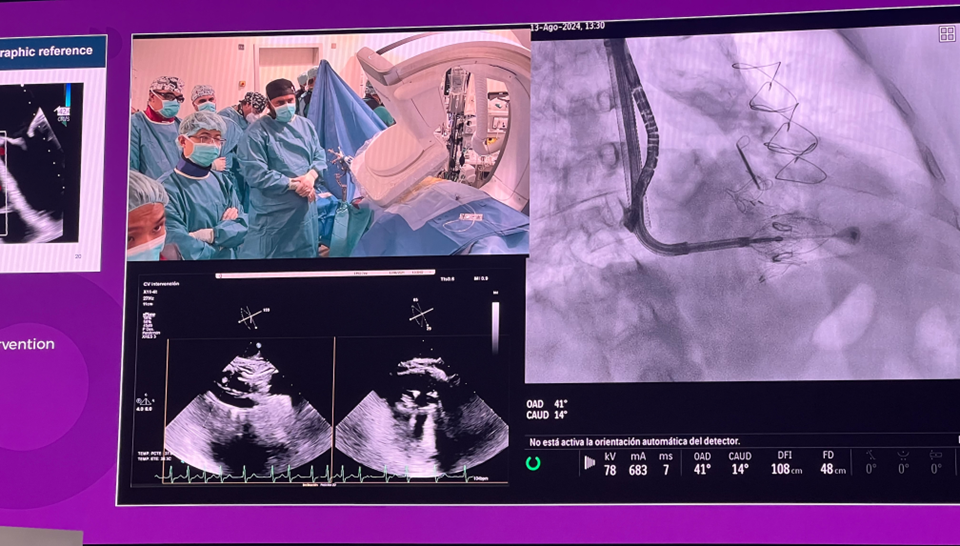

隨后由來自西班牙維哥-阿爾瓦羅昆奎羅醫院(Hospital Álvaro Cunqueiro, Vigo, Spain)的 Rodrigo Estevez-Loureiro 教授在大會主會場的經導管介入瓣膜新技術環節,帶來了一例 LuX-Valve Plus 手術錄播,對手術植入的步驟和關鍵要點進行了詳細深入的介紹。同時,臺上的多位討論嘉賓也結合他們的 LuX-Valve Plus 手術經驗進行了深入的探討。來自香港瑪麗皇后醫院(Queen Mary Hospital, Hong Kong, China)的 Simon Lam 教授分享了 LuX-Valve Plus 在術前有起搏導線病人中的植入經驗,來自巴西圣保羅(Rede D'Or São Luiz, São Paulo, Brazil)的 Vinicius Esteves 教授補充了 LuX-Valve Plus 獨特的非徑向支撐力設計,能夠實現非常低的術后起搏器植入率,來自法國波爾多大學醫院(CHU de Bordeaux, Bordeaux, France)的 Lionel Leroux 教授則分享了其在LuX-Valve Plus歐洲臨床試驗過程中,對于大尺寸瓣環植入的優異結果。